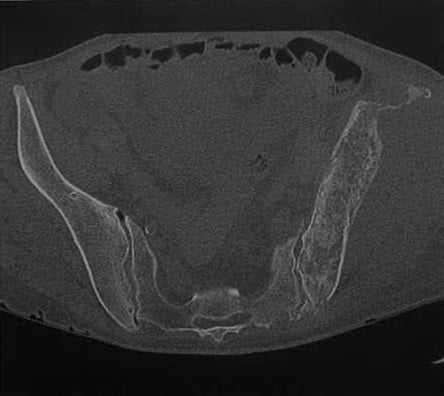

(Слева) ПЭТ/КТ, аксиальная проекция: у пациента с первичной лимфомой кости, после проведенного лечения визуализируется новая зона накопления в передней ости левой подвздошной кости (слева, справа).

(Справа) КТ, аксиальная проекция, костный режим: у того же пациента в этой области визуализируется размытая зона склероза без признаков костной деструкции. При этом первичном заболевании у пациента костный мозг расценивался, как «орган» поражения, поэтому возникновение новых очагов в других костях правильнее будет называть рецидивом, а не метастазами. (Слева) Классический пример дифференциальной диагностики с мелкокруглоклеточной опухолью. Визуализируются множественные литические деструктивные очаги в области таза, а также комбинированный литическо-склеротический очаг в бедренной кости.

Женщина 64 лет с первичной неходжкинской лимфомой кости. На КТ в аксиальной проекции обнаруживается распространенная деструкция кости со смешанной литической и инфильтративной структурой, в сочетании со склеротическим компонентом в левой подвздошной кости.